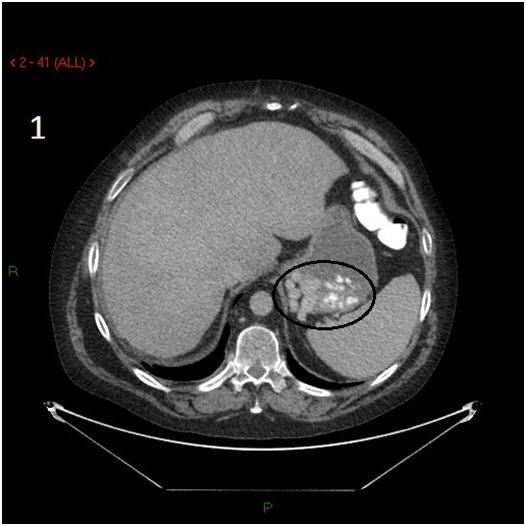

A fifty four years old male presented with intermittent upper gastrointestinal (GI) bleeding. His past medical history was significant for severe heart failure, coronary artery bypass surgery, mechanical aortic and mitral valve replacement, chronic atrial fibrillation, end stage renal failure on hemodialysis, and pacemaker implantation. He had no past history of liver disease, and his liver viral serology was negative. The patient was passing dark stool, and required daily blood transfusions and withdrawal of anticoagulation upon initial stabilization. Upper gastrointestinal endoscopy showed varices at the cardiac portion of the stomach with stigmata of recent bleeding. Due to anatomic location of the varices in the cardia, endoscopic band ligation was not technically possible. Abdominal CT scan showed varices in the vicinity of gastric fundus with spontaneous collateral venous shunt connecting left renal vein and stomach (Figures 1-3).

Figure 1 Abdominal CT scan, transverse view, showing a conglomerate of varices outside and inside the stomach wall (outlined with a circle).